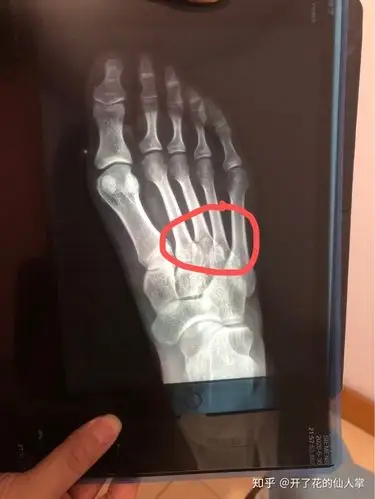

跖骨34基底骨折